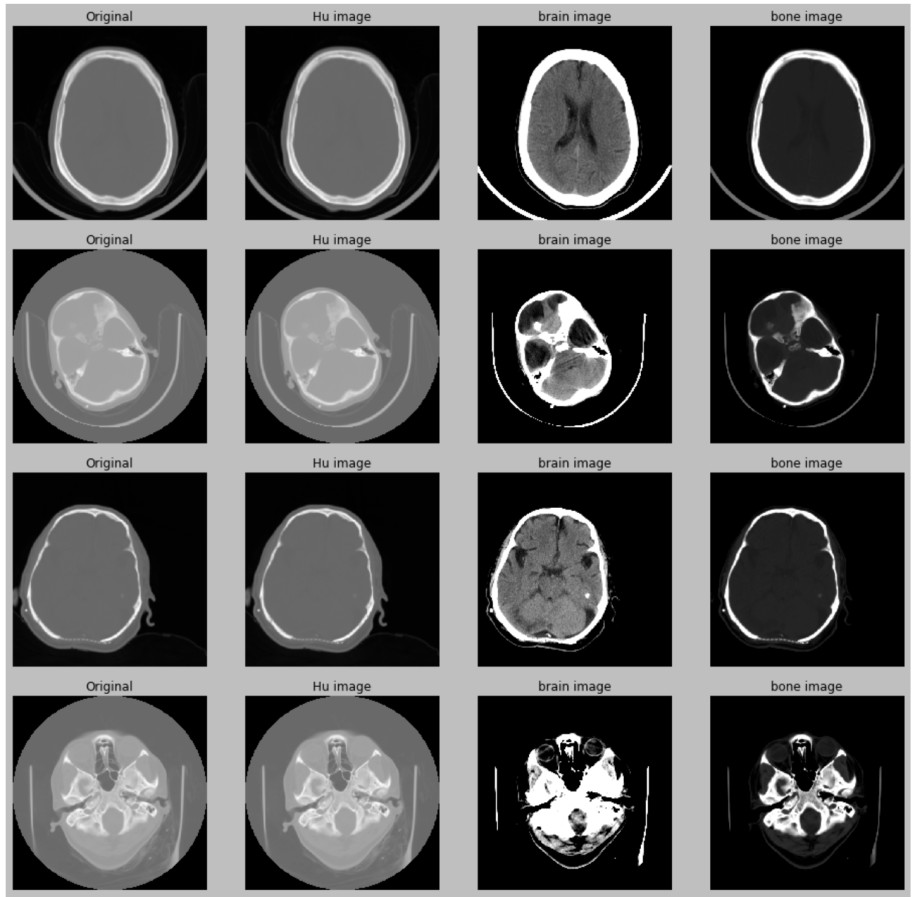

Hounsfield Units

Different Tissues, Different Intensities

Window/Level

optimized for soft tissue

optimized for lung

optimized for bones

All viewers support this!